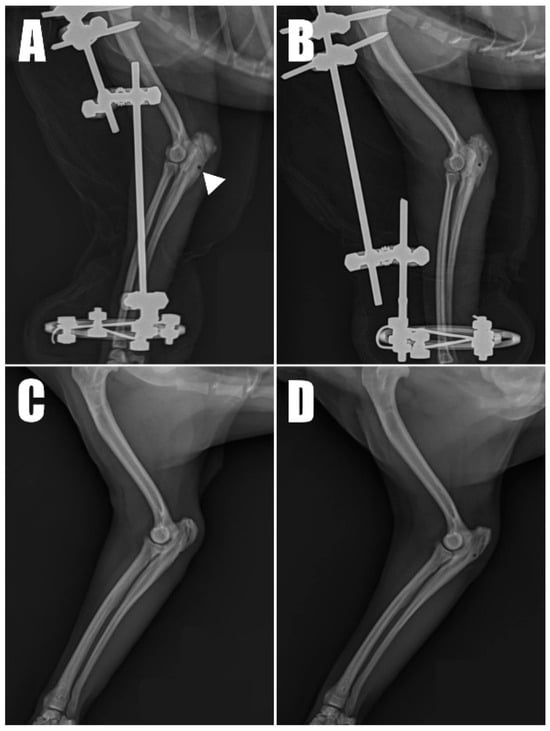

Postoperative radiographs and ultrasound images (Figure 6) were taken to confirm the position and connectivity (Figure 7) of the tendon on the olecranon. On the right side (Figure 6A), the transverse hole was observed to be close to the caudal cortex, while the remaining bone tunnels were confirmed to have been drilled as intended. For analgesia, remifentanil was continued for three days postoperatively at 0.1~0.3 ug/kg/min with constant rate infusion. The other postoperative therapy including antibiotics (amoxicillin and clavulanic acid, 12.5 mg/kg BID, for 14 days/Clindamycin, 11 mg/kg BID, for 14 days), NSAID (meloxicam, 0.1 mg/kg SID for 14 days), and gastrointestinal protectant (esomeprazole, 1 mg/kg SID for 14 days) were administered.

Radiography (Figure 6C,D) and ultrasonography (Figure 7C,D) six months postoperatively confirmed that the transverse hole of the right side healed without any complications, and the bilateral triceps brachii tendons were well-maintained and attached to the olecranon, with no specific changes in internal echogenicity or echotexture. MRI (Figure 8) showed mild inflammatory changes near the suture knot and fibrotic scar tissue within the tendon but confirmed firm attachment of the tendon to the olecranon. Three years following the surgery, the patient exhibited no signs of functional loss (Video S2) or pain, confirming the long-term success of the treatment. The owner expressed satisfaction with the clinical outcomes.

Figure 6. Immediate postoperative radiograph of the (A) right forelimb showing the transverse hole (arrowhead) in the caudal aspect of the ulna. (B) A corresponding image of the of the left forelimb. Six-month postoperative radiograph of the (C) right and (D) left forelimb.